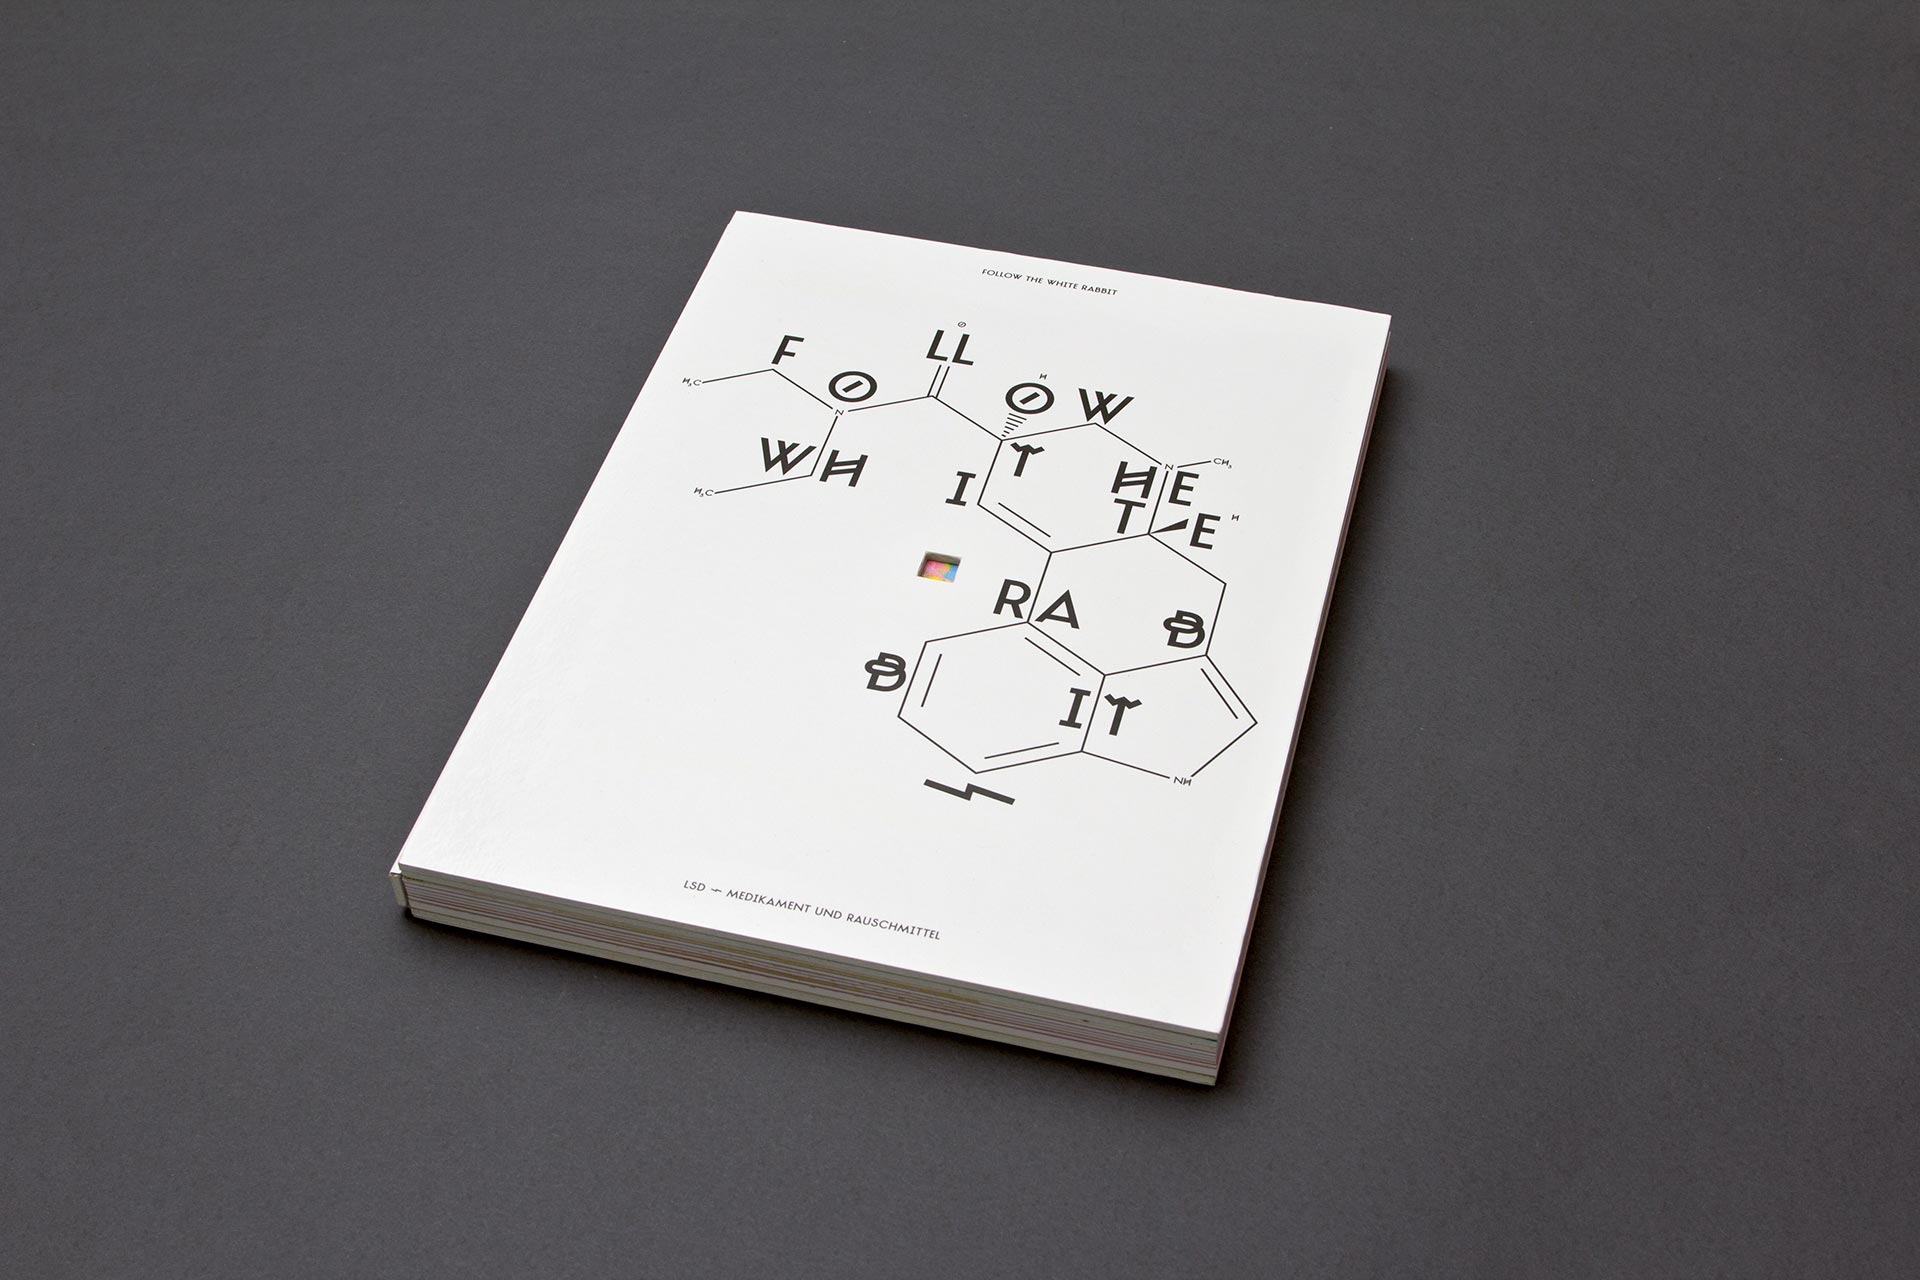

Follow The White Rabbit

ID # 23816

Fachhochschule Mainz, DE

professor : Isabel Naegele

Sara Ellinger

contact :

www.saraellinger.de